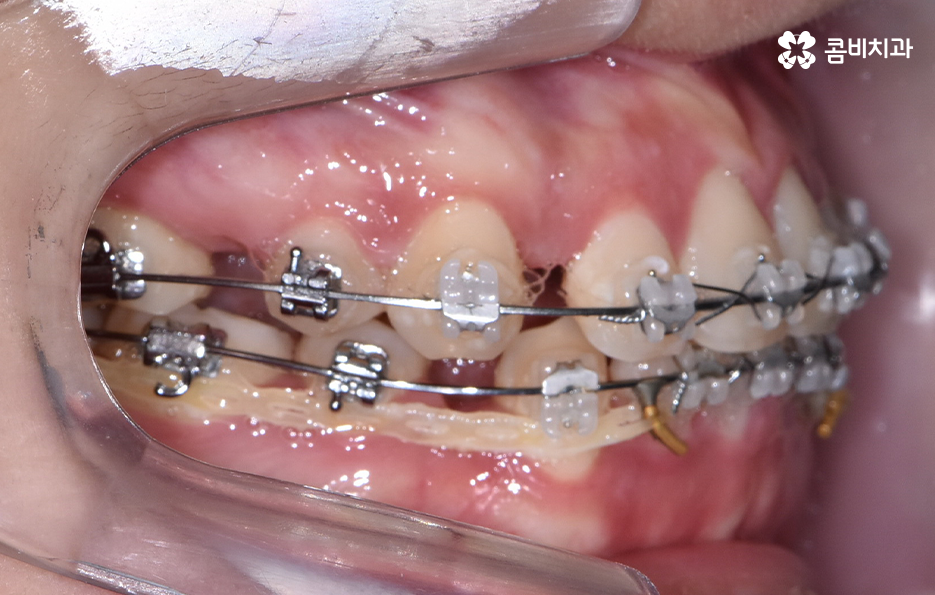

출처 아카이브 열기치아교정의 목적은 다양하지만 돌출입을 개선하고자 하는 목적성을 갖는 경우 발치가 필요한 경우가 대부분이라고 할 수 있는데요. 그 이유는 입이 나와 있는 돌출입을 개선하기 위해서는 앞니 부분이 뒤 쪽으로 들어가야 돌출입이 개선되기 때문인데 치아를 안쪽으로 이동시키기 위한 공간 확보를 위해 발치가 필요한 경우가 많은 거예요.

돌출입을 개선하기 위한 교정 치료의 사례에도 돌출입발치교정 사례가 많은 이유도 치아의 발치를 통해 앞니를 후방 이동시키는 치아 교정의 원리가 있기 때문이라고 설명할 수 있어요

오늘은 돌출입발치교정 통해서 치열도 가지런하게 교정하고 얼굴형의 변화뿐 아니라 교합까지 잘 맞물려서 건강하게 치아교정을 하는 방법에 대해 알아볼 거예요